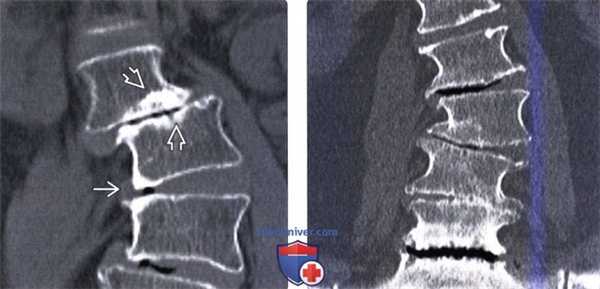

(Слева) КТ, фронтальный срез: случай левостороннего сколиоза грудопоясничного перехода и правосторонняя сколиотическая деформация поясничного отдела позвоночника. КТ с много -плоскостными реконструкциями изображения достаточно информативны в отношении оценки состояния позвоночника в целом и влияния листеза позвонков на состояние спинномозгового канала и нервных образований.

(Справа) Рентгенограммы позвоночника в прямой и боковой проекциях: случай протяженного спондилодеза грудного и поясничного (до уровня L5) отделов позвоночника. В большинстве случаев стабилизацию не рекомендуется заканчивать на уровне сегментов, смежных с сегментами с выраженными дегенеративными изменениями, особенно если здесь имеет место фиксированный наклон или подвывих позвонка. Проксимальный сегмент конструкции не должен оканчиваться ниже проксимальной структуральной грудной дуги искривления. Окончание протяженной конструкции на уровне L5 может привести в дальнейшем к выраженной дегенерации диска L5-S1. Поперечные коннекторы используются в первую очередь для придания конструкции ротационной стабильности.